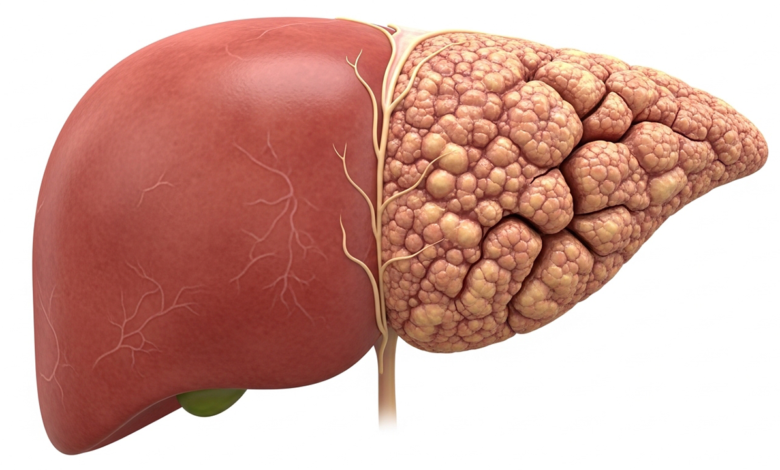

تليف الكبد

يعتبر تليف الكبد حالة مرضية مزمنة وخطيرة تحدث نتيجة لتكون نسيج ندبي يحل محل خلايا الكبد السليمة، مما يعيق قدرة العضو على أداء وظائفه الحيوية بشكل تدريجي،

تحدث عملية التليف عندما يتعرض الكبد لإصابات متكررة أو مزمنة حيث يحاول العضو إصلاح نفسه بشكل مستمر، وتؤدي هذه العملية إلى تكون نسيج ندبي ليفي يعيق تدفق الدم داخل الكبد ويقلل من قدرته على معالجة العناصر الغذائية والهرمونات والأدوية وإزالة السموم،

ومع مرور الوقت يتراكم هذا النسيج الندبي ويدمر بنية الكبد الطبيعية، مما يؤدي إلى انخفاض تدريجي في وظائفه الحيوية حتى الوصول لمرحلة الفشل الكبدي التي لا رجعة فيها.